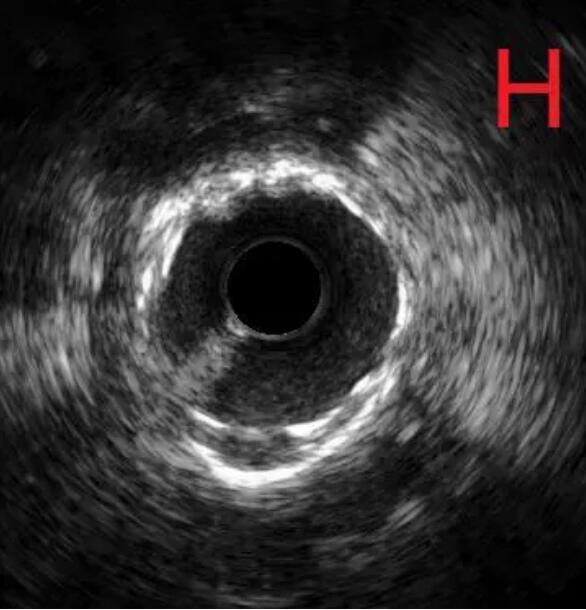

对冠状动脉造影及IVUS图像进行综合判断,目前已经具备安全进行冠状动脉支架治疗的条件,于是在病变处植入支架治疗,随后在IVUS指导下采用后扩球囊改善贴壁情况,顺利完成手术(图G、H)。